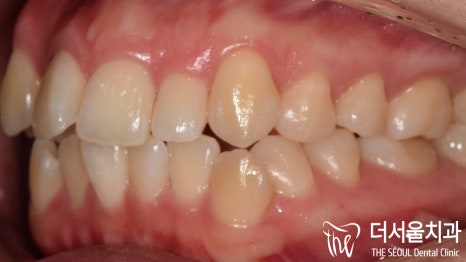

측면에서 바라보니,

앞으로 더 많이 뻐드러져 있는 것이 확인이 되죠?

이런 증세들 때문에

입술이 튀어나온 것 처럼 보여지게 되는 겁니다.

측면에서 바라봤을 때에도, 전과는 다르게

뻐드러짐이 없어진 것이 확인 됩니다.